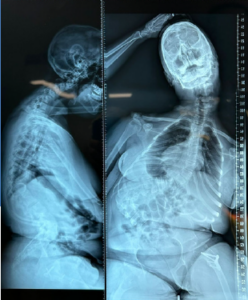

Уникальная экспертиза в нейрохирургии

Команда врачей-хирургов совместно с врачом-нейрохирургом, д.м.н. Баклановым А.Н. провела коррекцию сколиоза пациентке 14 лет с диагнозом ДЦП. Во время 6-ти часовой операции произошла большая кровопотеря, была перелита кровь и плазма.

Через 10 дней пациентка самостоятельно вышла из клиники, подарив команде хирургов, анестезиологов, медсестер счастливую улыбку и детскую книгу собственного сочинения.